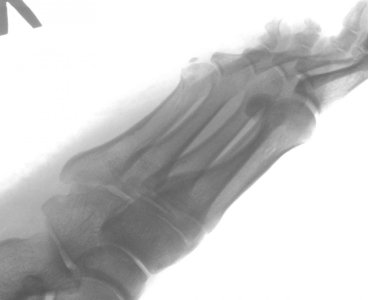

Здравствуйте. Мне 38 лет. Перелом 5-ой плюсневой.

Приложенные снимки - на следующий день после случившегося. Сразу в гипс на 5 недель. Ни в травмпункте, ни в поликлинике лечащий врач даже на упоминали операцию.

Только в травмпункте доктор сказал "... с незначительным смещением, поэтому просто гипс на месяц."

Посмотреть вложение 13116 Посмотреть вложение 13117